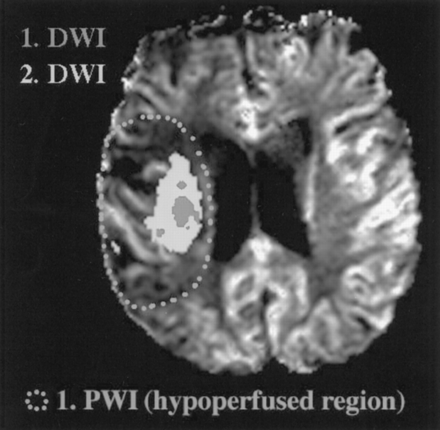

基于先前建立缺血半影和出版的特点,1,5,11我们开发了一个操作性定义的组织梗塞的风险使用回顾性方法的进展。第一个发现的病变扩散研究表明在我们的操作模型缺血性核心(图3和图4⇓)。初始扩散之间的不匹配区域病变及其扩展了后续醉酒驾车研究后的24到72小时第一个定义操作半影。从第一天使用灌注研究,指标CBV(初始rCBV、峰值rCBV总rCBV)和流(rCBF) rMTT,以及ADC值测定在三个地区(见定义图3和图4⇓):1)酒后病变时间点1(代表我们的操作缺血性核心),2)之间的不匹配区域首次和后续醉酒驾车研究(代表我们的操作半影),和3)侧半球,影响严重的地区反映第一醉酒驾车病变程度和解剖位置。镜子地区必须在10%的醉酒驾车病变的大小必须在同一时间点1,对侧半球的解剖定位。排除可能从intrasulcal工件或蛛网膜下腔CSF,我们手动放置这些地区所有片上,他们可以被识别,并计算意味着跨片(加权体素)的数量为每个定义的操作区域。

图3。操作模型定义缺血半影。第一个发现的病变扩散研究表明该地区能源的衰竭和类似于操作缺血性核心在我们的模型中。这种扩散的扩大病变(后续扩散研究)到大hypoperfused地区运营半影在这项研究。

均值(±标准平均误差(SEM))放大扩散异常在整个集团的376.6%(±206.5)比较第一次醉酒驾车和随后的酒后驾车,这是平均48(±6)小时后。醉酒驾车发生异常的扩大在该地区的低灌注的患者。所有患者的异常灌注区域大于驾车在初始扫描时间点异常。的平均体积异常灌注(使用MTT异常灌注异常的标志)是96.6毫升(±16.9)和醉酒驾车的异常是28.6毫升(±8.3)在初始时间点和59.2毫升(±15.4)在第二个时间点。二十二岁的25例有慢性t2加权扫描完成平均量66.6毫升(±15.9)。异常的平均增加慢性T2体积与最初的醉酒驾车相比体积在整个组患者467.0% (±182.4)。图4演示了一个代表病人的研究人群与皮质醉酒驾车病变和更大的一个小灌注异常,包括一个主要部分的大脑中动脉的领土。的扩散增大66%(比较第一天和第二天)发生在oligemic领土。减去醉酒驾车更扩大病变的病变在第一天的后续研究代表了缺血半影操作模型。